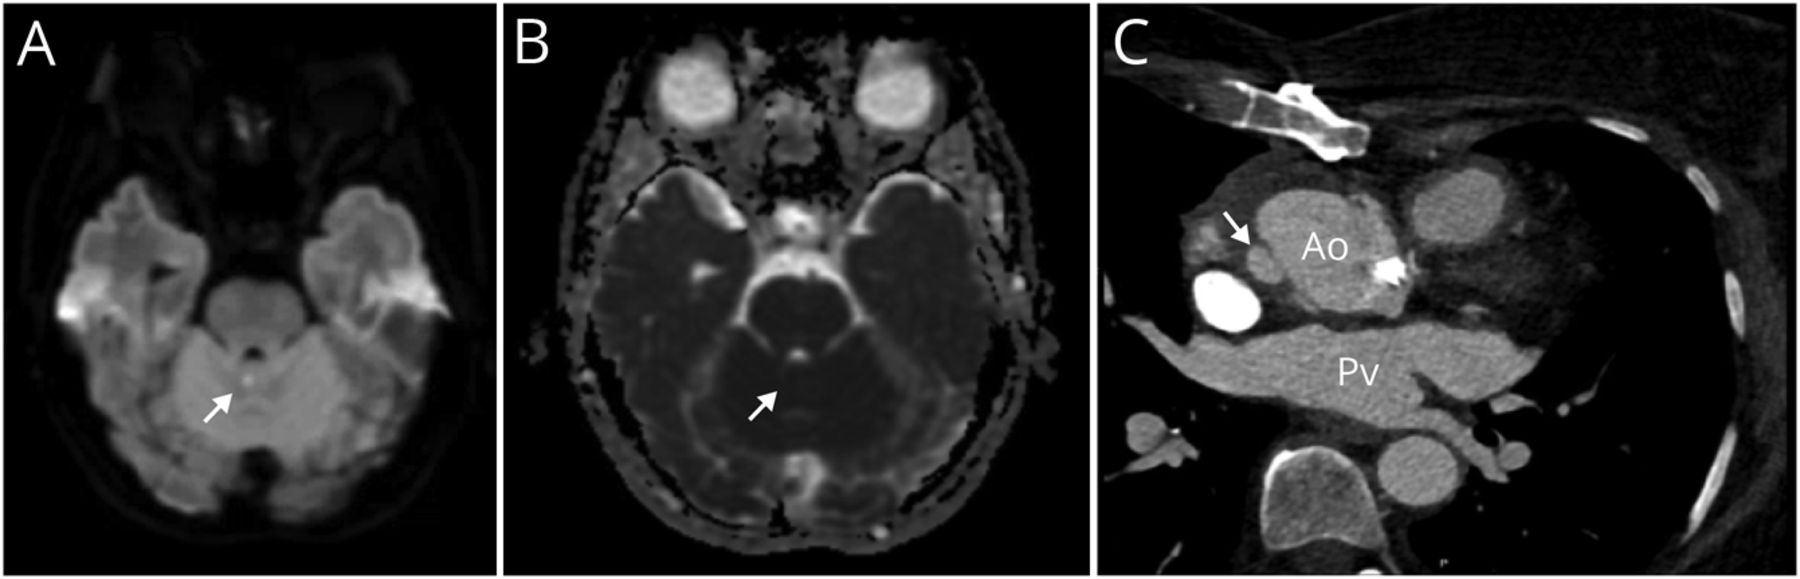

例描述

65岁女性,高血压、高脂血症、升主动脉瘤修补、瓣膜置换术、围术期房颤(未抗凝),出现突发性失衡。患者在跑步机上经历急性步态不稳,无眩晕。她抓住栏杆,保持在中线;除此之外,她向右倾斜。检查显示过去指向和步态共济失调,无构音障碍或眼震。脑MRI示小上蚓梗死。MRA未见明显狭窄。胸部CTA显示已知的主动脉假性动脉瘤增加(数字).这种假性动脉瘤不会形成血栓或成为栓塞源;她继续服用阿司匹林,没有抗凝。步态不稳和眩晕是小脑梗死的常见表现1;在累及蚓部的病变中可见孤立的侧推。2